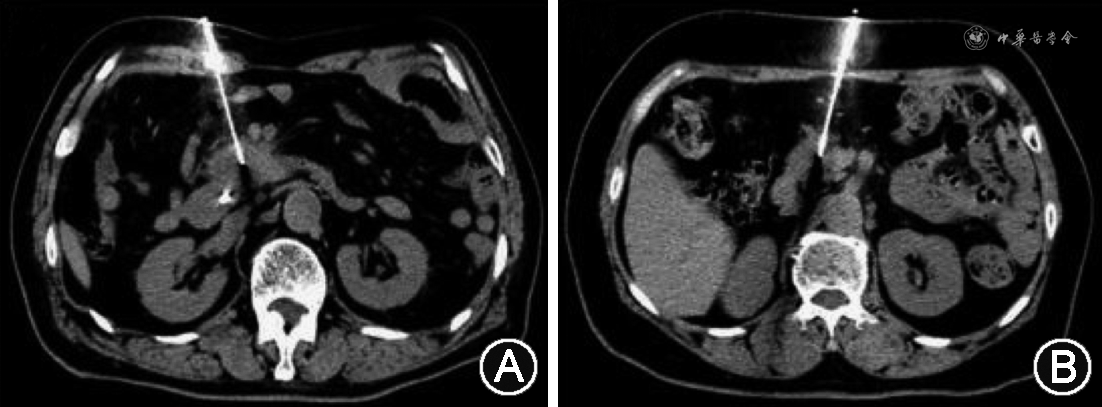

回顾性分析郑州大学第一附属医院2019年1月至2022年1月接受CT引导下经皮穿刺活检胰腺占位患者的临床资料。(1)纳入标准:①术前影像显示胰腺占位病变,需要明确病理诊断;②影像考虑恶性病变,需要进行放疗、化疗等抗肿瘤治疗;③影像学无法明确诊断;④穿刺活检后接受手术治疗、抗肿瘤治疗或随访期间明确诊断;⑤经皮穿刺活检后检查、检验资料完整。(2)排除标准:①各种方式均无法明确诊断;②无随访结果;③活检后检查、检验资料不完整。根据纳入标准、排除标准,采用连续纳入方法共纳入367例患者,其中男211例,女156例,年龄18~87(60.7±11.8)岁。根据术中是否经腹腔脏器分为经脏器路径(图1)组[142例,其中男84例,女58例,年龄18~86(60.6±12.6)岁]和非经脏器路径(图2)组[225例,其中男127例,女98例,年龄21~87(60.7±11.3)岁]。经脏器路径组中有28例(7.6%)经肝、57例(15.5%)经胃、24例(6.5%)经小肠、33例(9.0%)经结肠。本研究通过郑州大学第一附属医院伦理委员会许可(2022-KY-597),患者知情同意豁免。

1. 路径选择:术中根据病变位置选取体位,CT扫描(必要时行增强扫描),结合术前增强CT或MRI确定穿刺路径,应用2%利多卡因进行局部浸润麻醉。根据术中CT扫描图像设计穿刺路径,若有非经脏器路径则选择非经脏器路径;若穿刺路径被脏器遮挡,无法避开时则选择经脏器路径。常用的经脏器路径包括经肝脏、胃、小肠和结肠。

2. 进针方法:所有操作均在CT引导下采用“分步进针”方法进针。非经脏器路径可采用“迂回”进针、钝针分离或水分离等技术避开脏器。经脏器路径:第一步进针穿刺至腹膜,确定进针方向;第二步穿刺至危险脏器边缘再次确定进针方向;第三步穿刺拟要经过脏器;第四步穿刺靶病变。进行操作时,避免反复多次地穿过脏器,例如在进行调整进针方向时,避免退至经过脏器外;在进行切割活检时,要确定同轴穿过肠管或胃壁,避免活检枪切割肠壁或胃壁。